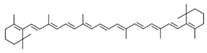

| Sr. No. | Name | PubChem ID | MF | MW | Canonical SMILES | Structure |

|---|---|---|---|---|---|---|

| 1 | Apigenin | 5280443 | C15H10O5 | 270.24 | C1=CC(=CC=C1C2=CC(=O)C3=C(C=C(C=C3O2)O)O)O |  |

| 2 | Caffeic acid | 689043 | C9H8O4 | 180.16 | C1=CC(=C(C=C1C=CC(=O)O)O)O |  |

| 3 | Catechin | 9064 | C15H14O6 | 290.27 | C1C(C(OC2=CC(=CC(=C21)O)O)C3=CC(=C(C=C3)O)O)O |  |

| 4 | Chlorogenic acid | 1794427 | C16H18O9 | 354.31 | C1C(C(C(CC1(C(=O)O)O)OC(=O)C=CC2=CC(=C(C=C2)O)O)O)O |  |

| 5 | Digalacturonic acid | 439694 | C12H18O13 | 370.26 | C1(C(C(OC(C1O)OC2C(C(C(OC2C(=O)O)O)O)O)C(=O)O)O)O |  |

| 6 | Ferullic acid | 445858 | C10H10O4 | 194.18 | COC1=C(C=CC(=C1)C=CC(=O)O)O |  |

| 7 | Gallic acid | 370 | C7H6O5 | 170.12 | C1=C(C=C(C(=C1O)O)O)C(=O)O |  |

| 8 | Iso-quercetin | 10813969 | C21H20O12 | 464.4 | C1=CC(=C(C=C1C2=C(C(=O)C3=C(C=C(C=C3O2)O)O)OC4C(C(C(C(O4)CO)O)O)O)O)O |  |

| 9 | Luteolin | 5280445 | C15H10O6 | 286.24 | C1=CC(=C(C=C1C2=CC(=O)C3=C(C=C(C=C3O2)O)O)O)O |  |

| 10 | Myricetin | 5281672 | C15H10O8 | 318.23 | C1=C(C=C(C(=C1O)O)O)C2=C(C(=O)C3=C(C=C(C=C3O2)O)O)O |  |

| 11 | p-coumaric acid | 637542 | C9H8O3 | 164.16 | C1=CC(=CC=C1C=CC(=O)O)O |  |

| 12 | Protocatechuic acid | 72 | C7H6O4 | 154.12 | C1=CC(=C(C=C1C(=O)O)O)O |  |

| 13 | Quercetin | 5280343 | C15H10O7 | 302.23 | C1=CC(=C(C=C1C2=C(C(=O)C3=C(C=C(C=C3O2)O)O)O)O)O |  |

| 14 | Resorcinol | 5054 | C6H6O2 | 110.11 | C1=CC(=CC(=C1)O)O |  |

| 15 | Rutin | 5280805 | C27H30O16 | 610.5 | CC1C(C(C(C(O1)OCC2C(C(C(C(O2)OC3=C(OC4=CC(=CC(=C4C3=O)O)O)C5=CC(=C(C=C5)O)O)O)O)O)O)O)O |  |

| 16 | β-Carotene | 5280489 | C40H56 | 536.9 | CC1=C(C(CCC1)(C)C)C=CC(=CC=CC(=CC=CC=C(C)C=CC=C(C)C=CC2=C(CCCC2(C)C)C)C)C |  |

| 17 |  | 222284 | C29H50O | 414.7 | CCC(CCC(C)C1CCC2C1(CCC3C2CC=C4C3(CCC(C4)O)C)C)C(C)C |  |